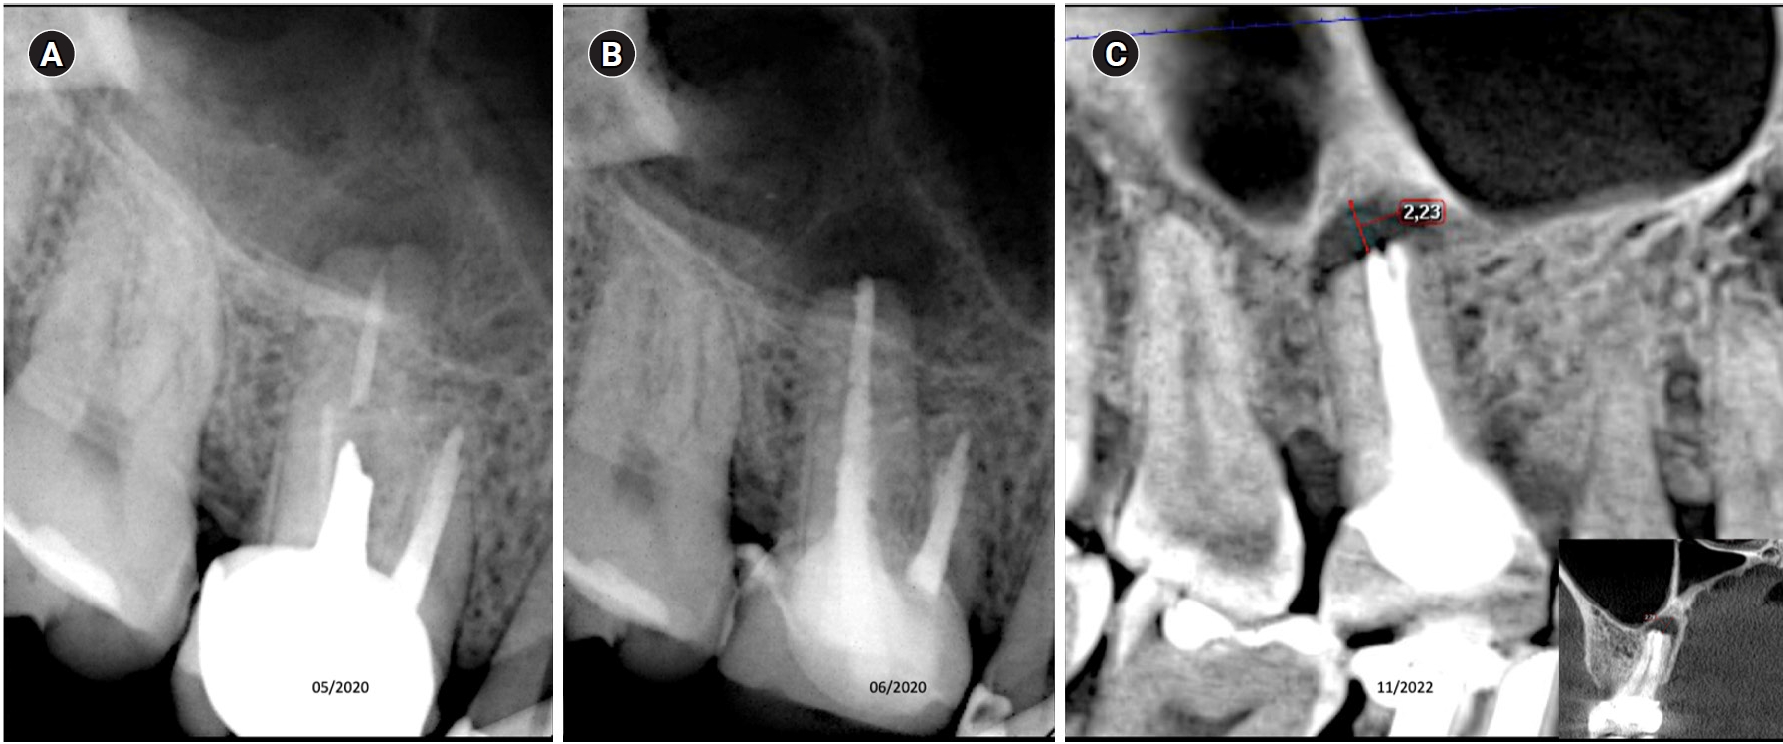

Tooth 16 with a diagnosis of previously initiated endodontic treatment and acute periapical abscess. (A) Diagnostic X-ray. (B) Immediate after obturation. (C) Tomographic control after 30 months, showing the apical lesion in the same manner as in the initial X-ray, considered a failure.